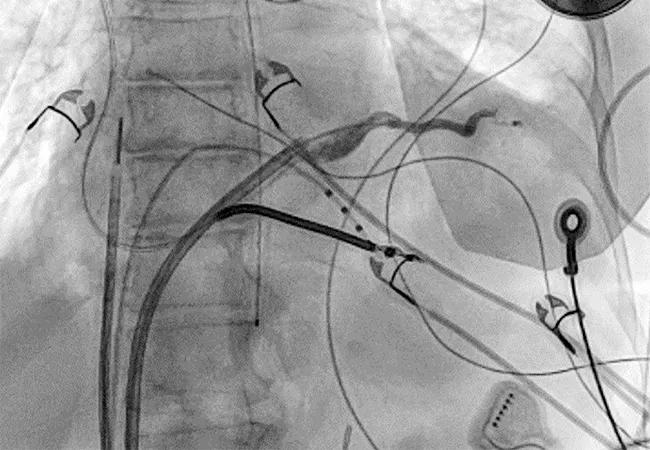

Once separation of the pericardial space is achieved, subxiphoid epicardial access can be conducted targeting the area of largest pericardial separation as seen by fluoroscopy (Figure 4). A needle preloaded with a wire is used to prevent pericardial deflation after access.

Video showing epicardial access targeting the area of largest pericardial separation on fluoroscopy

Figure 4. Video showing epicardial access targeting the area of largest pericardial separation on fluoroscopy.